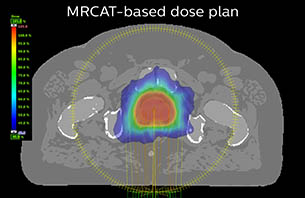

A 77-year-old male with prostate cancer cT3aN0M0, Gleason 8 and PSA 52 μg/L referred to androgen deprivation and radiation therapy with a prescribed dose of 50 Gy to the pelvic lymph node regions and 76 Gy to the prostate.

MR-only simulation workflow The 3D T1W FFE mDIXON sequence provides in-phase, water and fat images in one acquisition. Target and organs-at-risk are delineated on the 3D T2W TSE images. Prostate GTV is shown in orange, PTV in purple. The 3D bFFE sequence is used by the planner to mark the position of the fiducial markers (gold anchors) and contours are transferred to the digitally reconstructed radiographs (DRRs).

Based on the 3D T1W mDIXON images, MR-based density maps (MRCAT) are automatically generated. The VMAT (Volumetric Modulated Arc Therapy) plan is generated in TPS, based on MRCAT as primary image set. During the commissioning phase, dosimetric agreement between MRCAT-based and CT-based dose plans was studied and differences in the PTV dose were found to be minimal (<1% for most patients). Average difference in PTV mean values was 0.8% over the study group (n=62).